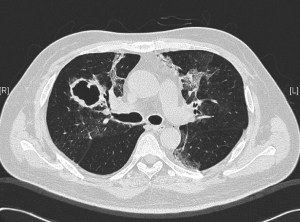

This is the same middle-aged man presented in the previous clinical vignette. He had undergone allogeneic stem cell transplantation (allo-HSCT) for underlying B-cell leukemia, with subsequent acute graft-versus-host disease (GVHD) of the liver. This was complicated 6 months later by RSV pneumonitis as previously described. His recovery was slow and required oxygen support even 3 weeks after the start of the RSV infection. A repeat CT showed cavities in both lung fields, with resolution of the prior ground-glass changes. These cavities appeared in the regions of the lungs previously affected by RSV. He was otherwise afebrile, with a slight cough and exertional dyspnea (requiring oxygen support) but has no other symptoms.

The repeat CT thorax showed multiple irregular, thick-walled cavities in both lungs. Medscape has a nice article on the various differentials of cavitary lung lesions. Various bacterial, fungal and mycobacterial organisms are able to cause such changes in an immunocompromised patient, but the most likely cause in this particular setting is infection caused by a mould belonging to Aspergillus spp. This can be diagnosed indirectly via serum or broncho-alveolar lavage fluid testing for galactomannan – a component of the Aspergillus spp. fungal cell wall (although the former is not particularly sensitive), or biopsy of the wall of a cavity. Treatment upon confirmation of diagnosis is with antifungal therapy. Voriconazole is currently the drug of choice – amphotericin formulations are only available via the intravenous route and the liposomal formulations are generally extremely expensive with equivalent or poorer outcomes compared to voriconazole.